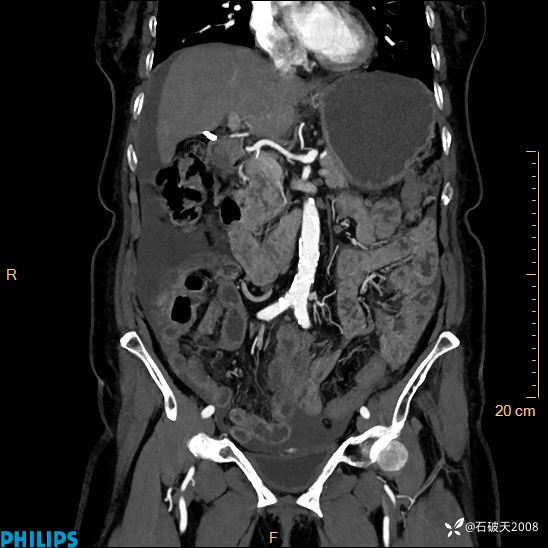

静脉期